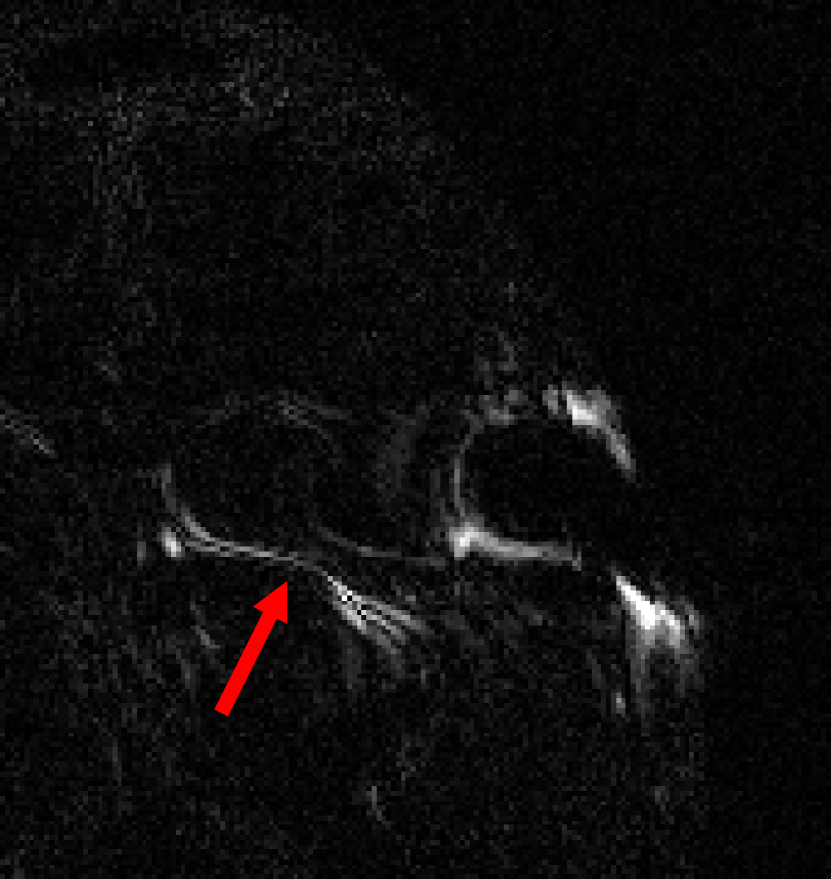

This result implies that random noise can also produce undesirable effects. In Fig. 3 we show several examples of this effect. For the first DL method, mean zero Gaussian noise causes the NN reconstruction map to hallucinate, by artificially removing an image feature (indicated by the red arrow). In the second case, certain image independent, small mean Gaussian noise causes severe instabilities in the recovered image. Notice that the noise causes the second DL method to exhibit completely nonphysical artefacts, which could be easily identified by a practitioner as a failure mode. Yet for the first method it creates seemingly realistic artefacts (hallucinations). Such pernicious artefacts may be impossible to detect.

Hallucinations with zero-mean Gaussian noise Instabilities w.r.t. to Gaussian noise with image independent mean

Noisy image: Noisy image:

|x+v|𝑥𝑣|x+v| |x+v|𝑥𝑣|x+v|

(full size) (cropped)

Refer to caption Refer to caption

DeepMRI-net: DeepMRI-net:

|Ψ(A(x+v))|Ψ𝐴𝑥𝑣|\Psi(A(x+v))| |Ψ(Ax)|Ψ𝐴𝑥|\Psi(Ax)|

(cropped) (cropped)

\begin{overpic}[width=433.62pt]{plots/im_noise1_fact_3_rec_worst_100_place_2_crop.png} \put(68.0,42.0){\color[rgb]{1,0,0}\definecolor[named]{pgfstrokecolor}{rgb}{1,0,0}\vector(1,4){6.0}} \end{overpic} Refer to caption

AUTOMAP: AUTOMAP:

Ψ(Ax+e0)Ψ𝐴𝑥subscript𝑒0\Psi(Ax+e_{0}) Ψ(Ax+e1)Ψ𝐴𝑥subscript𝑒1\Psi(Ax+e_{1})

(full size) (full size)

Ψ(Ax+e2)Ψ𝐴𝑥subscript𝑒2\Psi(Ax+e_{2}) Ψ(Ax+e3)Ψ𝐴𝑥subscript𝑒3\Psi(Ax+e_{3})

Figure 3: (Hallucinations and instabilities due to random noise) Two DL methods exhibit hallucinations and instabilities due to random noise. On the left, the DeepMRI-net [66] reconstruction map is unstable to mean-zero Gaussian noise v𝑣v. In this case, the NN hallucinates by removing a key image feature (see the red arrow). On the right, the AUTOMAP [82] reconstruction map is unstable to Gaussian noise. The noise vector e0subscript𝑒0e_{0} is drawn from a zero-mean Gaussian distribution, whereas the mean of the distribution, used to generate e1,e2subscript𝑒1subscript𝑒2e_{1},e_{2} and e3subscript𝑒3e_{3}, is based on three worst-case noise vectors computed for AUTOMAP with respect to a different image. This makes the mean is image independent. As we can see, the instability of the map produces noticeable artefacts. The measurement matrix in these experiments is a subsampled Fourier transform with 33% (left) and 60% (right) subsampling, respectively. See §A for further information.